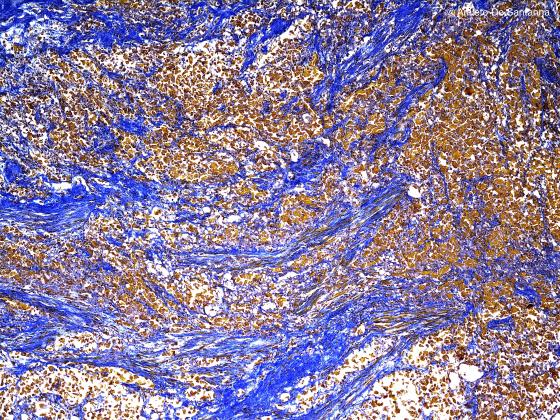

Figura C38. Prostata umana

Figure C38. Human prostate gland. Dense connective tissue made up of interwoven fibers, stained light blue, and interspersed smooth muscle fibers, stained brown. Ignesti X40